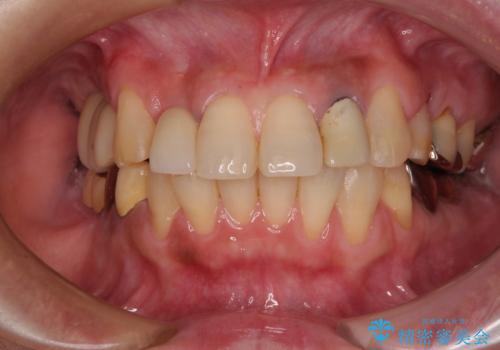

抜歯即時埋入インプラントによる補綴治療の特徴は、短期間であることや処置数が少ないことが挙げられます。また、表側の歯肉の陥凹を避けることができるというメリットがあります。しかしながら、今回は歯根破折の程度が酷く、やや膨らみを失うこととなりましたが、スムーズに治療を終えることができました。

臼歯部は前歯以上に炎症が酷く、抜歯即時埋入不可と判断されましたが、従来法よりは短期間で終えることができました。